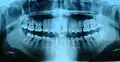

Зу́бы — органы в ротовой полости человека, служащие для первичной механической обработки пищи.

В норме у человека имеется от 28 до 32 зубов. Различают молочные (временные) и постоянные зубы.

Во временном прикусе (молочные зубы) присутствует 8 резцов, 4 клыка и 8 моляров — всего 20 зубов. У детей они начинают прорезаться в возрасте от 3 месяцев. В период от 6 до 13 лет молочные зубы постепенно заменяются постоянными, в этот период прикус является сменным.

Постоянный прикус состоит из 8 резцов, 4 клыков, 8 премоляров и 8—12 моляров. В редких случаях наблюдаются дополнительные, сверхкомплектные зубы (как молочные, так и постоянные)[1]. Отсутствие третьих моляров, называемых «зубами мудрости» является нормой, а сами третьи моляры увеличивающимся числом учёных уже считаются рудиментом, но это на данный момент спорный вопрос.